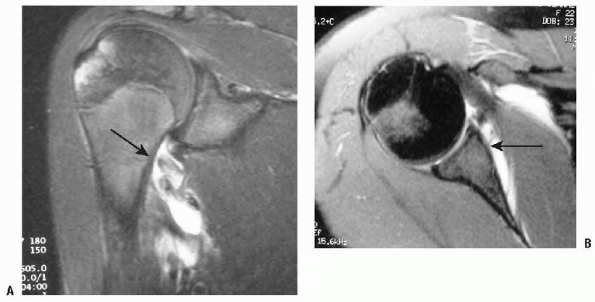

![]() |

Figure 17-8 A: MRI example of the HAGL lesion. B: MRI example of a Bankart lesion.

In identification of HAGL lesions, MRI in

the midsagittal coronal oblique plane shows the detachment of the

inferior glenoid labrum (IGL) and that the axillary pouch is converted

from a full distended U-shaped structure to a J-shaped structure, as

the IGL drops inferiorly (Fig. 17-8).P.221-

The appearance of a HAGL lesion with MRI

has been described as an avulsion fracture from the neocortex in the

humeral neck. A thin radiolucency is observed inferior to the anatomic

neck of the humerus, and once again the fluid-filled distended U-shaped

axillary pouch is converted into a J-shaped structure by the

extravasation of contrast material. The presence of this lesion may

also be a relative contraindication to an arthroscopic shoulder

stabilization procedure.